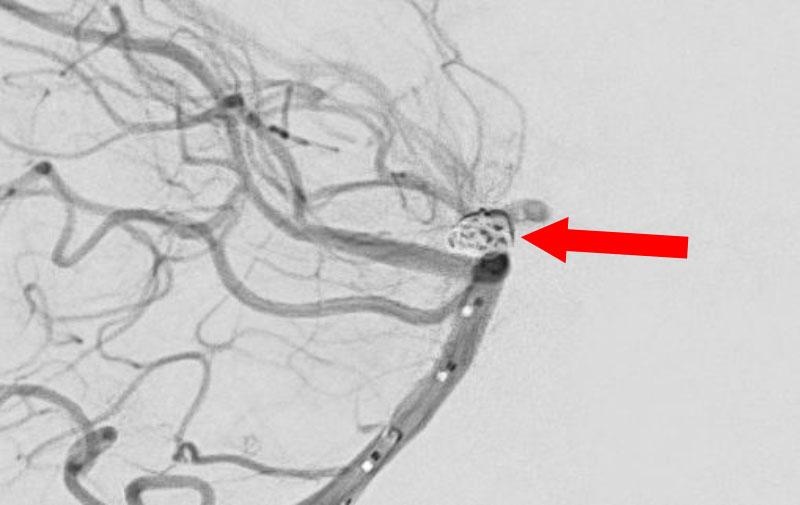

No.1631 手術前

No.1631 手術中

No.1631 手術後